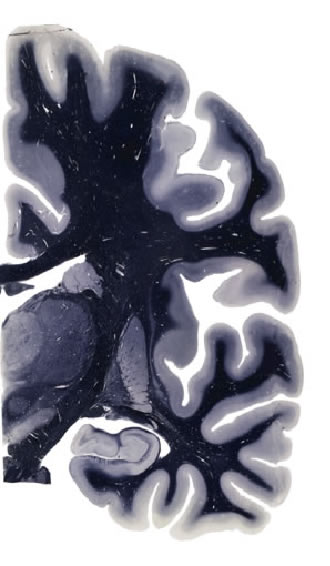

Hi-Resolution Sections · Cells (Nissl Staining) · Virtual Microscopy

Frontal sections (Nissl) from the Atlas Brain:

Slice ID:

r3-0702

Plate NR:

ca 35-36

Position:

18,6 mm